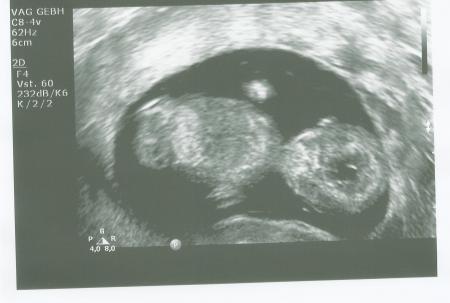

Huhu Mädels, auch ich war nach 4 1/2 Wochen endlich mal wieder beim FA und anscheinend ist es völlig normal, dass auch ich gestern starke Angst hatte, dass irgendwas nicht in Ordnung ist. Gerade zu Anfang der SS finde ich 4 Wochen warten echt schlimm... Aber es war alles super! Herz schlug nach wie vor und der FA war zufrieden. Ich wurde nun allerdings zum zweiten Mal nochmal zurück gestuft, sodass ich jetzt (leider) erst bei 11+2 bin, aber ganz egal, solange in meinem Bäuchlein alles ok ist. Der/die Kleine ist "schon" 4,3cm groß und es war echt faszinierend per US zu gucken. Selbst mein Mann war sprachlos und konnte nichts mehr sagen- so kenne ich ihn gar nicht ;-) Wünsche allen, die ihren Termin noch vor sich haben viel Spaß beim Baby-TV und drücke ganz fleißig alle Daumen, dass auch bei euch alles ok ist!

Ja, ich habe auch drei Bildchen mitgenommen! Hab es zwar schon eingescannt, aber ich möchte noch den oberen Rand entfernen, wo die ganzen Daten stehen... Ui, 06.03... auch noch sooooo lange hin! Ich sag ja: Vier Wochen können manchmal echt verdammt lange werden.

Also das Bild ist ja echt der Hammer. So niedlich. Vor allem die Öhrchen. ;-) ich hab keinen vier-wochen-Rhythmus, sondern alle zwei Wochen. Bin auch RisikoSS, wg. Übergewicht u. weil ich in der 5.ssw Blutungen hatte. Deswegen nehme ich auch Utrogest. Vier Wochen würde ich kaum aushalten. War letztem Freitag das letzte Mal. LG

Oh ja! Gerade wenn man liest wie viele sich leider wieder verabschieden mussten... Aber auch genau aus diesem Grund machen wir uns vllt auch alle etwas verrückt und haben Angst, dass bei uns auch irgendwas nicht ok wäre! Ich versuche nun die SS so weit es geht zu genießen! Und hoffe nach wie vor das Beste! Drei Wochen-Takt ist doch schön! Darf ich fragen wie es kam?! Hast du eine RisikoSS oder macht das der FA automatisch so? Und nun ein Bildchen noch von gestern ;-) Hoffe, dass es klappt mit dem Hochladen!

super, dass alles ok ist. Ein tolles Bild hast Du da. 4 Wochen würde ich gar nicht durchhalten. Ich bin jetzt am Anfang im 2-Wochen-Rhythmus da und dann schätze ich alle 3 Wochen. War beim letzten Mal auch so. Zum Schluss jede Woche. Ich bin allerdings Risiko SS, da ich in der Vorgeschichte eine stille Geburt in der 37. Woche hatte.

Boooaaah, wie süüüß ist das denn? Nee, bin keine Risikoschwangere. Meine FÄ macht das von sich aus. Sie hat da scheinbar in dem Takt "alles im Griff". So passt es ihr irgendwie besser, so wie dann am 13.03. die NFM.

Wow, echt süß Dein Krümel. Ich darf am Freitag wieder zur NFM. Da kann mein Mann endlich auch mal mitkommen. Freu mich schon. LG Tina